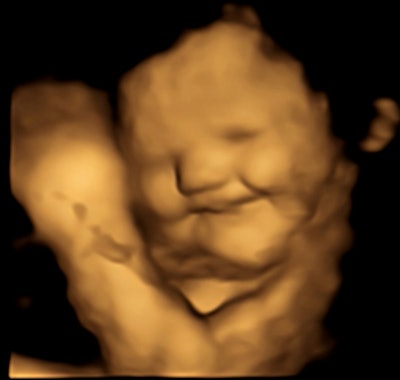

Four-dimensional ultrasound scans show evidence that fetuses at 32 to 36 weeks react positively or negatively to smell and taste, according to a study from the U.K. published on 21 September in Psychological Science.

Researchers led by Beyza Ustun from Durham University found via ultrasonic imaging that fetuses gave "cry-face" reactions to kale, which is bitter in taste, and "laughter-face" reactions to sweeter carrot after the mothers ingested capsules for each flavor.

The researchers found that the 35 fetuses exposed to carrot flavor showed "lip-corner puller" and "laughter face" expressions more frequently. Meanwhile, the 34 fetuses exposed to kale flavor showed more "upper-lip raiser," "lower-lip depressor," "lip stretch," "lip presser," and "cry-face" expressions.